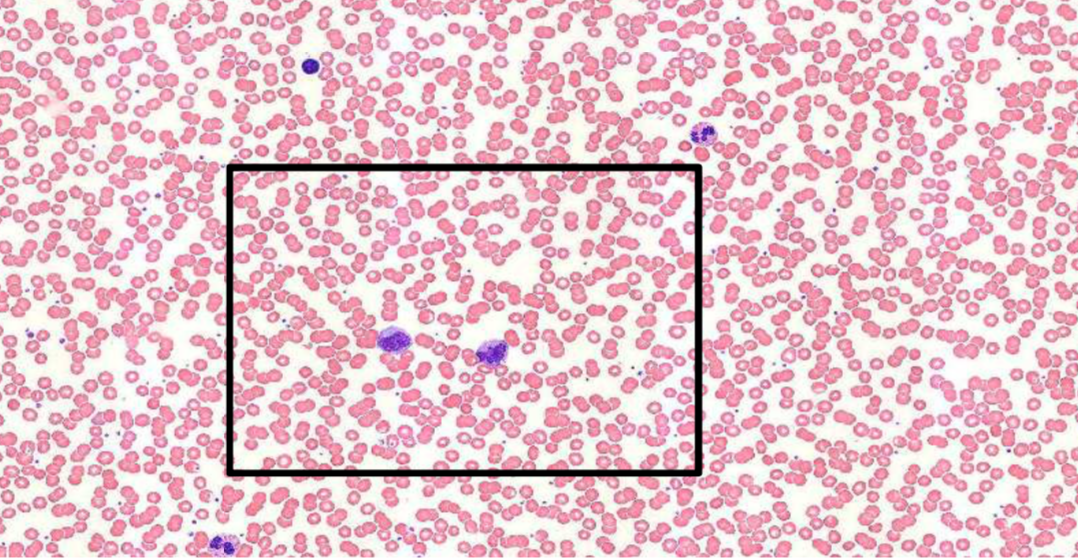

Sur cette coupe on dit dans la ronéo qu'on voit en haut à droite un PNE mais ça ressemblerait pas plutôt à PNN ? (et en bas à gauche on aurait plus un PNE)

Capture d’écran 2019-11-27 à 14.31.48.png